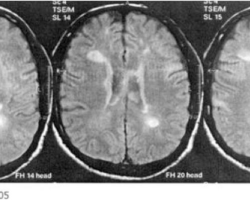

Sclérose en plaques